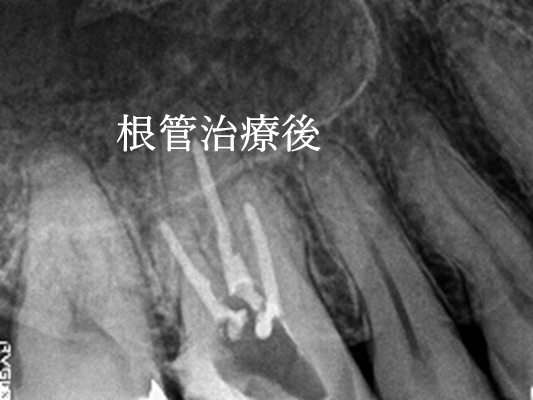

女性Mさん 70代(オールセラミック冠)

右前歯が動く。

治療内容

水平に破折していました。破折していた部分を取り除き、根管治療をし、ファイバーコアをいれ、オールセラミック冠を被せました。

所感

今まで、他の歯を治療した時は、すべてメタルフリーの治療をされていて、オールセラミック冠の良さを実感されていましたので、今回もオールセラミックを選択されました。

オールセラミック冠(失活歯):¥104,500(税込)

Before

破折した部分を取り除いたところ

After

根管治療後